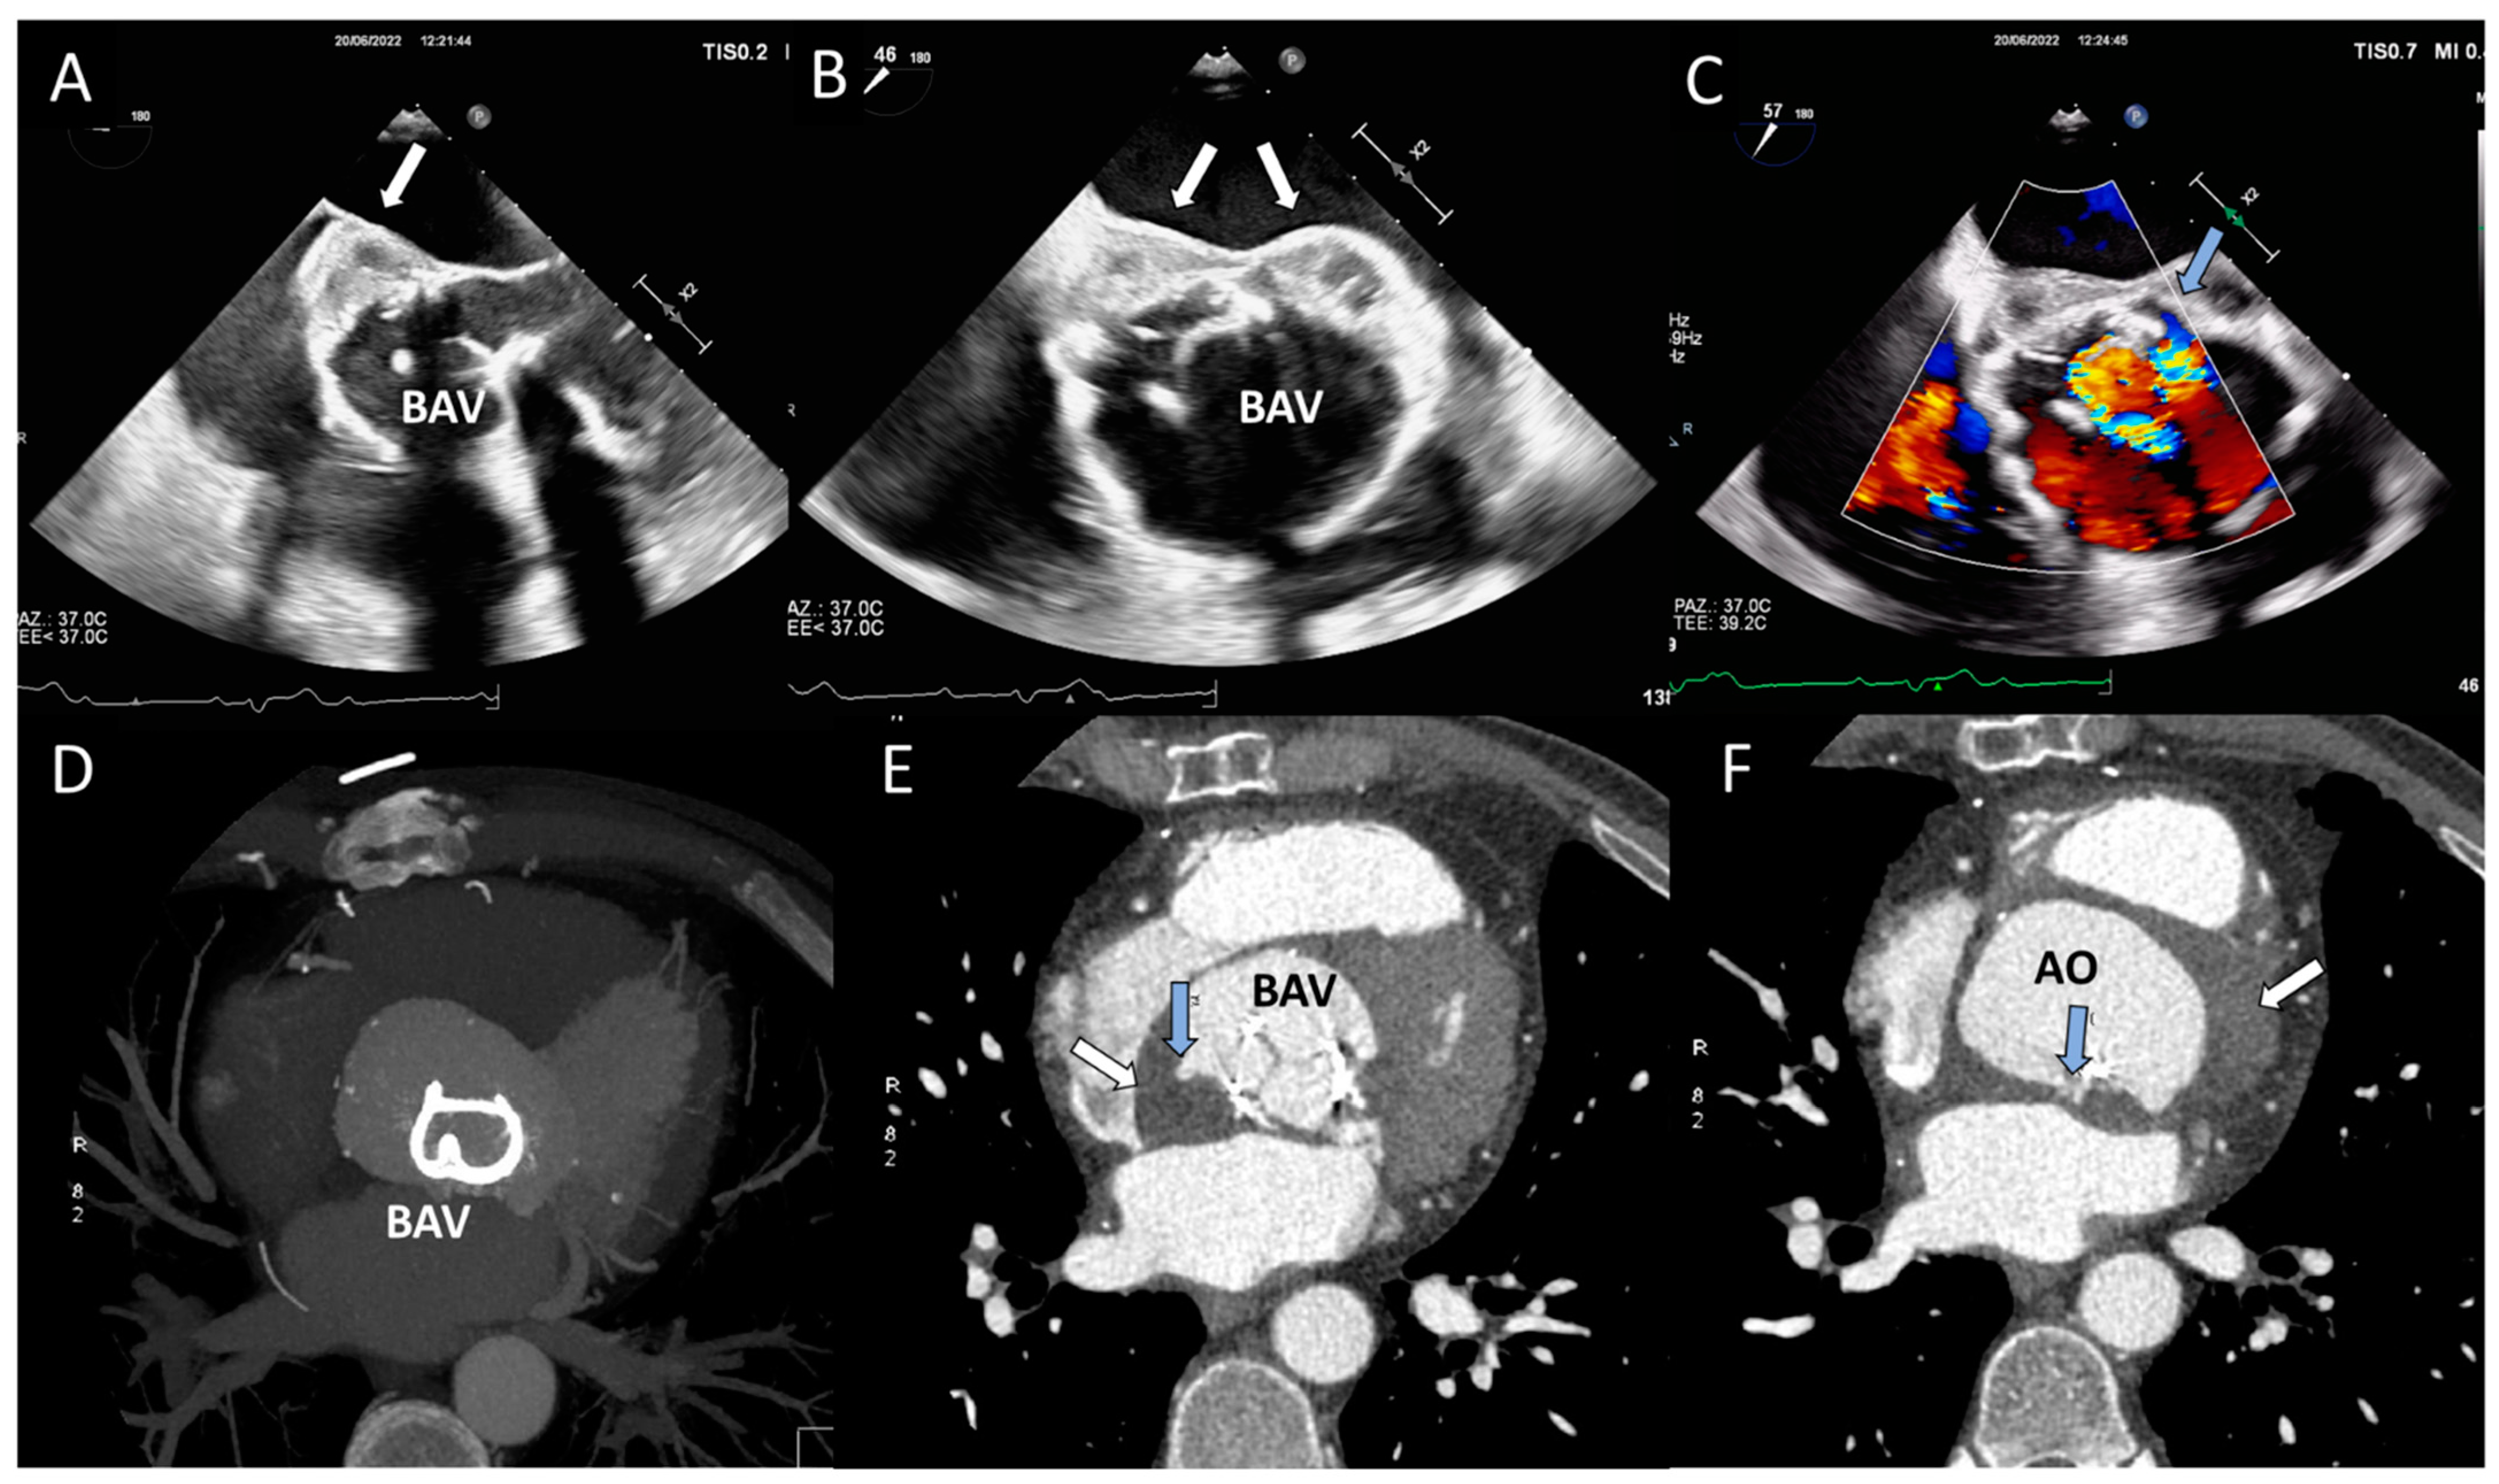

| TTE, TEE | Leaflet and/or ring thickening with diffuse or focal hyperechogenicity (calcifications). Reduced leaflet mobility. Leaflets’ fenestration, avulsion, or perforation. Stenosis or regurgitation. | Iso-hypoechogenic mass adherent to leaflets and ring, with leaflet thickening. Normal or reduced cusp mobility. More often, stenosis; regurgitation is uncommon. | Vegetations, diffuse or focal leaflets thickening, cusps perforation, wear or tear or cusp avulsion. Vegetation motion independent to cusps motion. Paravalvular complications: abscess, pseudo-aneurysm, fistula or dehiscence (and in some cases valve rocking) |

| CCT | Pannus (hypodense): HU ≥ 145; semicircular or circular structure located along leaflets’ surface or stent. Hyperdense leaflet thickening with or without calcifications, along with or without reduced mobility. | No calcifications. HU < 145. Hypoattenuated leaflet thickening (HALT), affecting (HAM) or reducing (RLM) leaflet motion. In some cases, large hypoattenuated mass. | Hypoattenuated mass adherent to leaflets or stent. Paravalvular complications: abscess, pseudo-aneurysm, fistula, or dehiscence. |